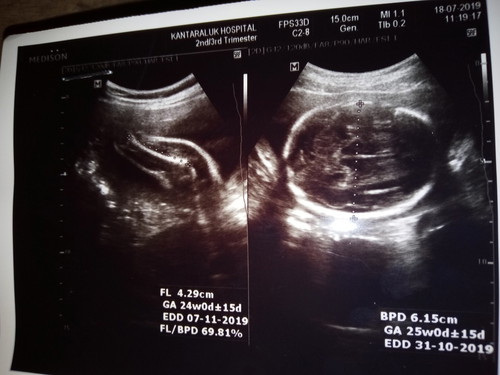

EFWค่ะ คือน้ำหนักช่วงวีคที่ซาว บ้านนี้ซาวมามีทั้งในใบสีขาวนี้เเล้วก็ใบสีดำที่บอกลักษณะลูกค่ะ

ของแม่ไม่มีบอกแต่ของเราจะบอกนน.รูปนี้ตอนท้อง18wค่ะนน.235g